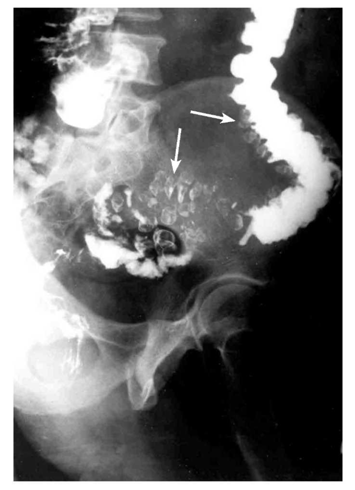

- חוקן בריום: בחולים בלא סיבוכים אפשר לראות סעיפים הבולטים מדופן הכרכשת. לאחר ההתרוקנות נשאר הבריום בסעיפים, והם בולטים בצילום הבטן (תצלום 11.6). בחולים הלוקים בדלקת, בחוקן בריום אפשר לראות עווית, בצקת של הדופן והדגמה של הסעיפים באזורים סמוכים. לפעמים קשה להבדיל מצב זה משאת של הכרכשת (תצלום 12.6). במחלה סעיפית אפשר לראות נגיעות של מקטע, עווית שלו וסעיפים במקומות אחרים.